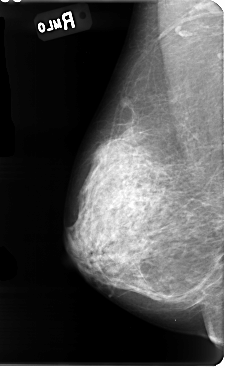

B_3085_1.RIGHT_MLO

RIGHT_MLO LINES 4784 PIXELS_PER_LINE 2920 BITS_PER_PIXEL 12 RESOLUTION 50 NON_OVERLAY